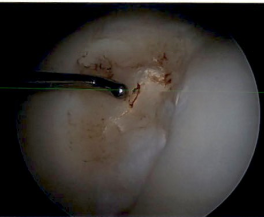

Debridement

Debridement patella chondral flap

Debridement trochlea chondral damage